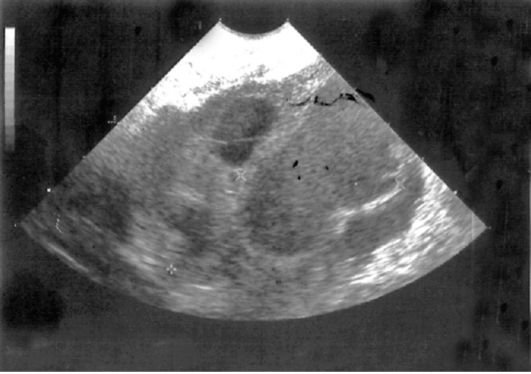

При воспалительном процессе повышаются показатели СОЭ и лейкоцитов. - УЗИ органов малого таза. Диагностическим критерием является наличие жидкости в области малого таза и внутри маточных труб, нечеткость контура яичника, кисты, признаки спаек, и болезные ощущения у пациентки при работе узиста датчиком.

- УЗИ внутренних половых органов. Что помогает выявить воспалительные изменения маточных труб и яичников и диагностировать другие осложнения, которые возможны при аднексите.